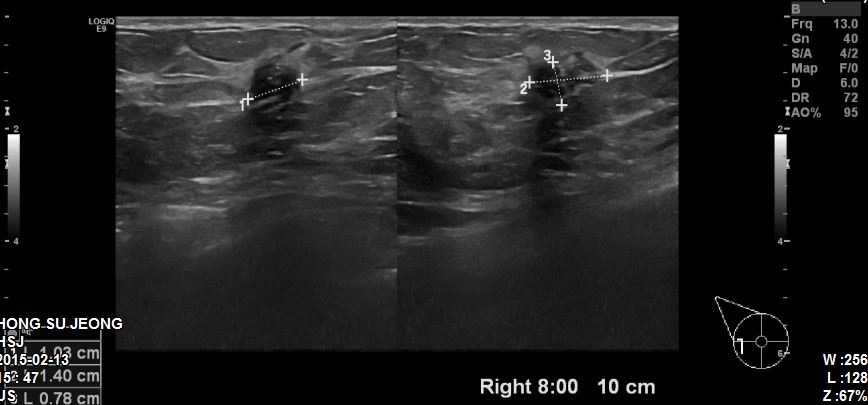

본원에 내원하신 70대 환자분이십니다.

우측 8시 방향에 1.40cm의 혹 조직검사 시행하였고

결과상 침윤성 유관암진단되었습니다.